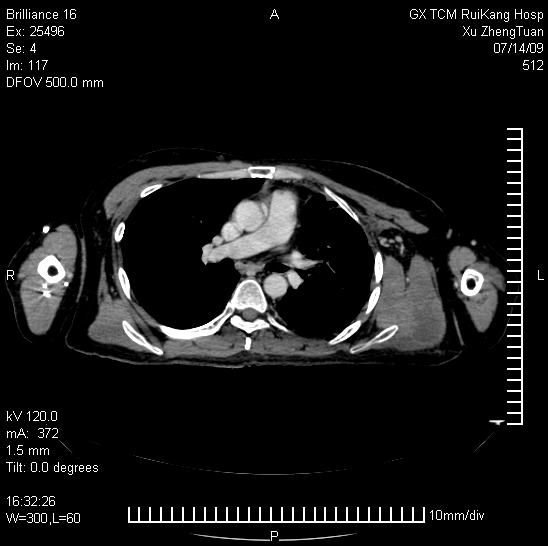

2009年2月初,许正团就抱着试试看的想法来到了广西瑞康医院。该院肿瘤一区主任练祖平教授和白广德教授看了患者带来的病历资料,他们认为,巨大肿瘤可采用射波刀放射治疗和氩氦刀冰冻治疗。先将巨大肿瘤逐渐杀灭后,遗留下来的肿瘤坏死组织再通过中药在体内慢慢吸收,同时运用中医特色防止肿瘤的复发。专家们提出了这个全新的治疗方案。许先生感到很震惊。此时他感到自己有救了……。他决定试一试。这时,许先生住进了瑞康医院,开始长达两个月的治疗。因患者胸部的肿瘤太大了,医生决定采用射波刀立体定向放疗联合氩氦刀微创冷冻治疗:位于左锁骨以下向左侧胸壁、胸腔侵犯的肿瘤,用氩氦刀冷冻治疗;位于左锁骨以上向左肺尖及左肩、左颈侵犯的肿瘤,用射波刀治疗。经过多次的治疗,终于将巨大肿瘤细胞杀灭了。住院两个月后,许先生在配合健脾益气、益肝补肾的中药内服为主,主要是尽快恢复两刀治疗所致的机体创伤。两刀治疗结束后,中药则以解毒散结、益气通络为治法,目的是消除机体形成肿瘤内环境因素,阻断肿瘤的生长,防治肿瘤的复发,初期尚配合针灸以促进左上肢机体功能恢复。自2009年5月后,患者已经开始回到原工作岗位上班,并坚持在门诊服用上述中药调理。

至今历时2年半时间,经过3次CT和磁共振检查,均提示该肿瘤逐渐缩小,最后一次复查(2011年8月15日CT)见肿瘤已经缩小至5cm×3cm,仍为坏死组织,左肺已经完全复张,左上肢功能已经完全恢复,没有发现新病灶。